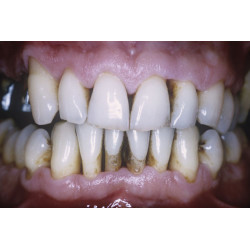

Sinais e sintomas da periodontite

A dor é geralmente ausente, a não ser que uma infecção aguda se desenvolva em uma ou mais bolsas periodontais, ou se houver periodontite associada ao HIV. A impactação alimentar nas bolsas pode causar dor durante as refeições. Placa bacteriana abundante, associada a hiperemia, edema e exsudato, é característica. As gengivas podem ser sensíveis e sangrar facilmente, e a respiração pode estar comprometida. À medida que os dentes amolecem, particularmente quando apenas um terço da raiz está no osso, a mastigação torna-se dolorosa.

Inspeção de dentes e gengiva, combinada à exploração das bolsas gengivais e aferição de suas profundidades, quase sempre é suficiente para o diagnóstico. Bolsas mais profundas que 4 mm indicam periodontite.

Radiografias dentais revelam perda do osso alveolar adjacente às bolsas periodontais.